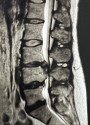

Стеноз спино-мозкового каналу, причини, симптоми, методи діагностики та лікування.

Грижа міжхребцевого диска – це стан, при якому тіло хребетного диска прориває оболонку (фіброзне кільце) і випинається назовні.